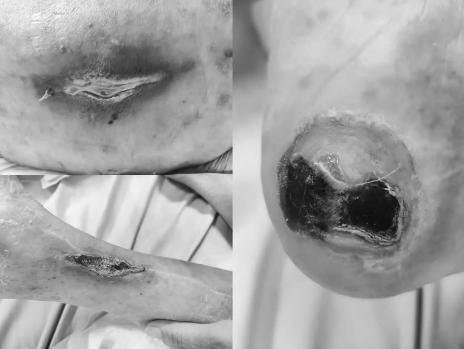

朱爷爷入院后,邓主任带领中西医结合科团队共同对其开展了全面身体评估。经评估发现,朱爷爷除存在肺部感染、软组织感染及泌尿道感染外,还患有2型糖尿病、高血压3级(极高危)、冠状动脉粥样硬化性心脏病、稳定型心绞痛、心功能不全、前列腺增生、不完全性偏瘫等多种基础疾病。此外,评估还显示其右腰背部、骶尾部、右小腿内侧及右足跟部位存在多处 Ⅲ 期压疮。

在诊疗与照护过程中,医疗团队围绕感染问题开展针对性处理;护理团队按照操作规范为压疮创面进行清创换药,开展创面护理;照护团队提供日常护理服务,包括定时协助翻身、身体清洁等,减少压疮相关风险。